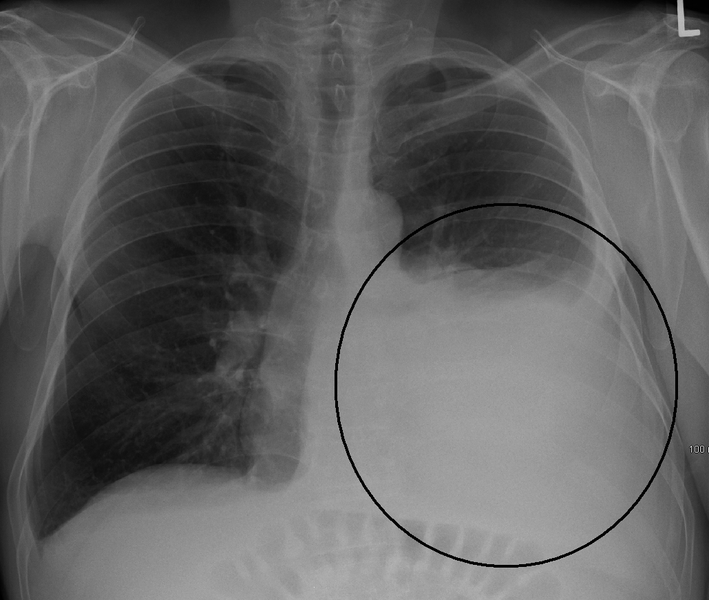

Malin plevral effüzyon (MPE) kanser nedeniyle akciğerin dış zarları arasındaki boşlukta sıvı birikmesidir, bu sıvı akciğerle göğüs kafesi arasını doldurur. Sıklıkla nefes darlığına neden olur. Tedavi seçenekleri olarak sıvının bir göğüs dreniyle boşaltılması, plevra boşluğuna kamera ile (torakoskopi) girilerek tedavi, ya da cilt altına giden bir tünelle (kalıcı plevral kateter) yarı kalıcı göğüs drenajıdır. Sıvının yeniden toplanmasını önlemek içim plevra boşluğuna kimyasal maddeler de uygulanabilir (plörodezi). Sıvının birikimini önlemek ve ağrı, nefes darlığı ve yaşam kalitesi gibi hastanın bildirdiği yan etkiler açısından hangi metodun en iyi olduğunu anlamak istedik.